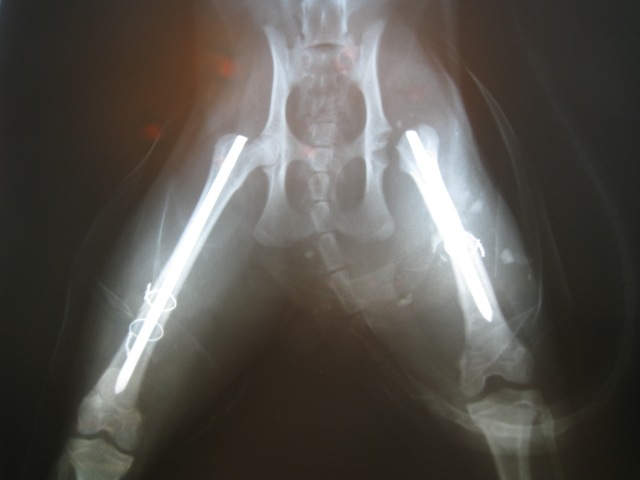

تاریخچه: گربه حمایتی پیدا شده توسط حامی احتمالاً به دلیل تصادف با وسیله نقلیه از ناحیه استخوان ران هر دو پا و مفصل رانی لگنی دچار شکستگی شده بود که در طی سه عمل جراحی در یک روز ترمیم شدند.

رادیوگراف تهیه شده قبل از جراحی رادیوگراف بعد از جراحی و سر به سر شدن کامل

همراه جراحی FHO سر استخوان ران